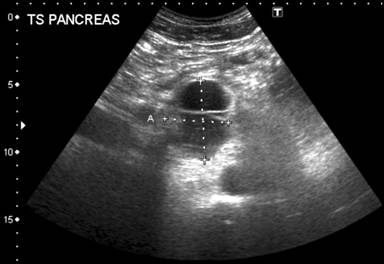

A 67-year-old man presented to the urologists with recurrent episodes of painless haematuria on the background of benign prostatic hypertrophy. An abdominal ultrasound scan demonstrated an incidental finding of a 5.7×4.7×4.4 cm thick walled avascular cystic structure with a thick septum in relation to the neck of the pancreas (Figure 1). Contrast enhanced computed tomography (Figure 2) confirmed the presence of a cyst related to the junction of the head and neck of the pancreas with otherwise normal architecture of the pancreas and no evidence of metastatic disease.

Figure 1. Ultrasound image of thick-walled septated cyst in relation to the neck of the pancreas. |